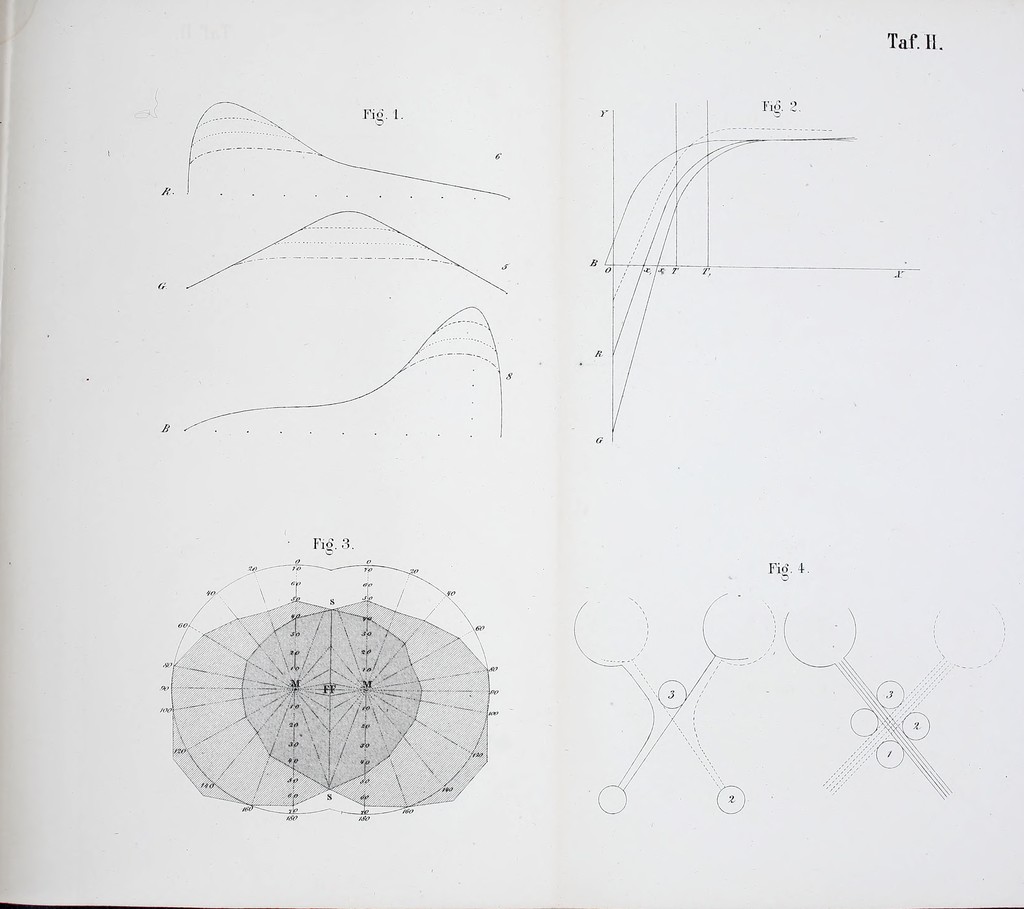

Die Lehre vom Gesichtsfelde und Seinen Anomalien : Eine physiologisch-kinische Studie / von Wilhelm Schoen.

- 1874